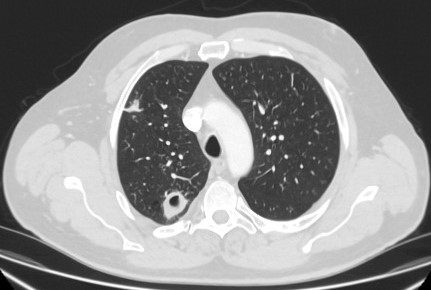

Computed tomography (CT) section capturing the transthoracic core biopsy needle targeting a left lower lobe lobulated nodule. Histopathology confirmed a well-differentiated squamous cell lung cancer

From the collection of Dr George Tsaknis, MD, PhD, FRCP(London), MRQA, MAcadMEd, PGCert; used with permission